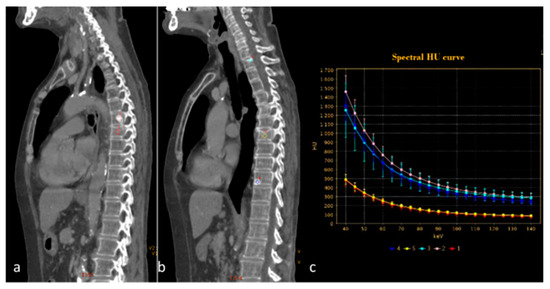

| Si-Mohamed et al. [67] Retrospective study | France | To assess whether VNC images derived from contrast dual-layer DECT images could replace TNC images for aortic intramural hematoma diagnosis in acute aortic syndrome imaging protocols by performing quantitative as well as qualitative phantom and clinical studies. | 21 | IQon, Philips Healthcare No C.I. | Dual-layer -DECT offers similar performances with VNC and TNC images for intramural hematoma diagnosis without compromise in diagnostic image quality. VNC imaging with dual-layer DECT reduces the number of acquisitions and radiation exposure in acute aortic syndrome imaging protocol. |

| Flors et al. [71] Retrospective study | USA | To evaluate the diagnostic performance of dual-source DECT in the detection of endoleaks after thoracic endovascular aortic repair for thoracic aortic aneurysm and to investigate if a double-phase (arterial and dual-energy late delayed phase) or a single-phase (dual-energy late delayed phase) acquisition can replace the standard triphasic protocol | 48 | Somatom Definition, Siemens Healthcare No C.I. | VNC and late delayed phase images reconstructed from a single DECT acquisition can replace the standard triphasic protocol in follow-up examinations after thoracic endovascular aortic repair, thereby providing a significant dose reduction. |

| Shuman et al. [72] Prospective study | USA | To compare DECT aortography using a 70% reduced iodine dose to single-energy CT aortography using a standard iodine dose in the same patient | 21 | Discovery CT750 HD; GE Healthcare, Waukesha, WI) One author received research grants from GE Healthcare No C.I. | 70% reduced iodine DECT aortography may result in similar aortic attenuation, CNR, SNR, and lower although acceptable subjective image scores when compared to standard iodine single-energy aortography in the same patient. |